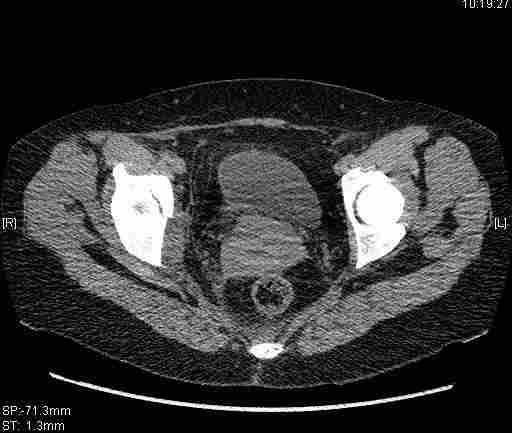

Женщина,58 лет, после ДТП 6 суток. Первично повреждение расценено как переломы ветвей лонной кости. После подтверждения повреждения вертлужной впадины,как чаще всего случается, вопрос встал о тактике. БОльшинство за консерватиное лечение.К сожалению кт у нас "во время" сломался. Прилагаю стандартные снимки вертлужки. У меня следующие вопросы к коллегам:1. Правильно ли рассценивать это повреждение как Т-образный перелом вертлужнй впадины?2. Можно ли добиться анатомической репозиции поверхности вертлужной впадины скелетным вытяжением в данном случае, если нет, что будет этому препятствовать?3. Если смещение останется таким как сейчас, через какое время появится необходимость эндопротезирования (по вашему опыту)?Спасибо.

имеется передний подвывих, головка нагружаемой зоной будет "тереться" о край фрагмента, связанного с осевым скелетом.

Вытяжение не поможет в любом случае, т.к. потянуть за одну переднюю колонну не получится. Есть вариант закрытого лечения, но для этого нужно наоборот сдавить крылья (скажем аппаратом), если больше переломов переднего полукольца нет, то передний подвывих уменьшится.

Удалось сегодня вывести пациентку в соседнюю больницу, где есть кт. Срезы сделаны только горизонтальные.

|